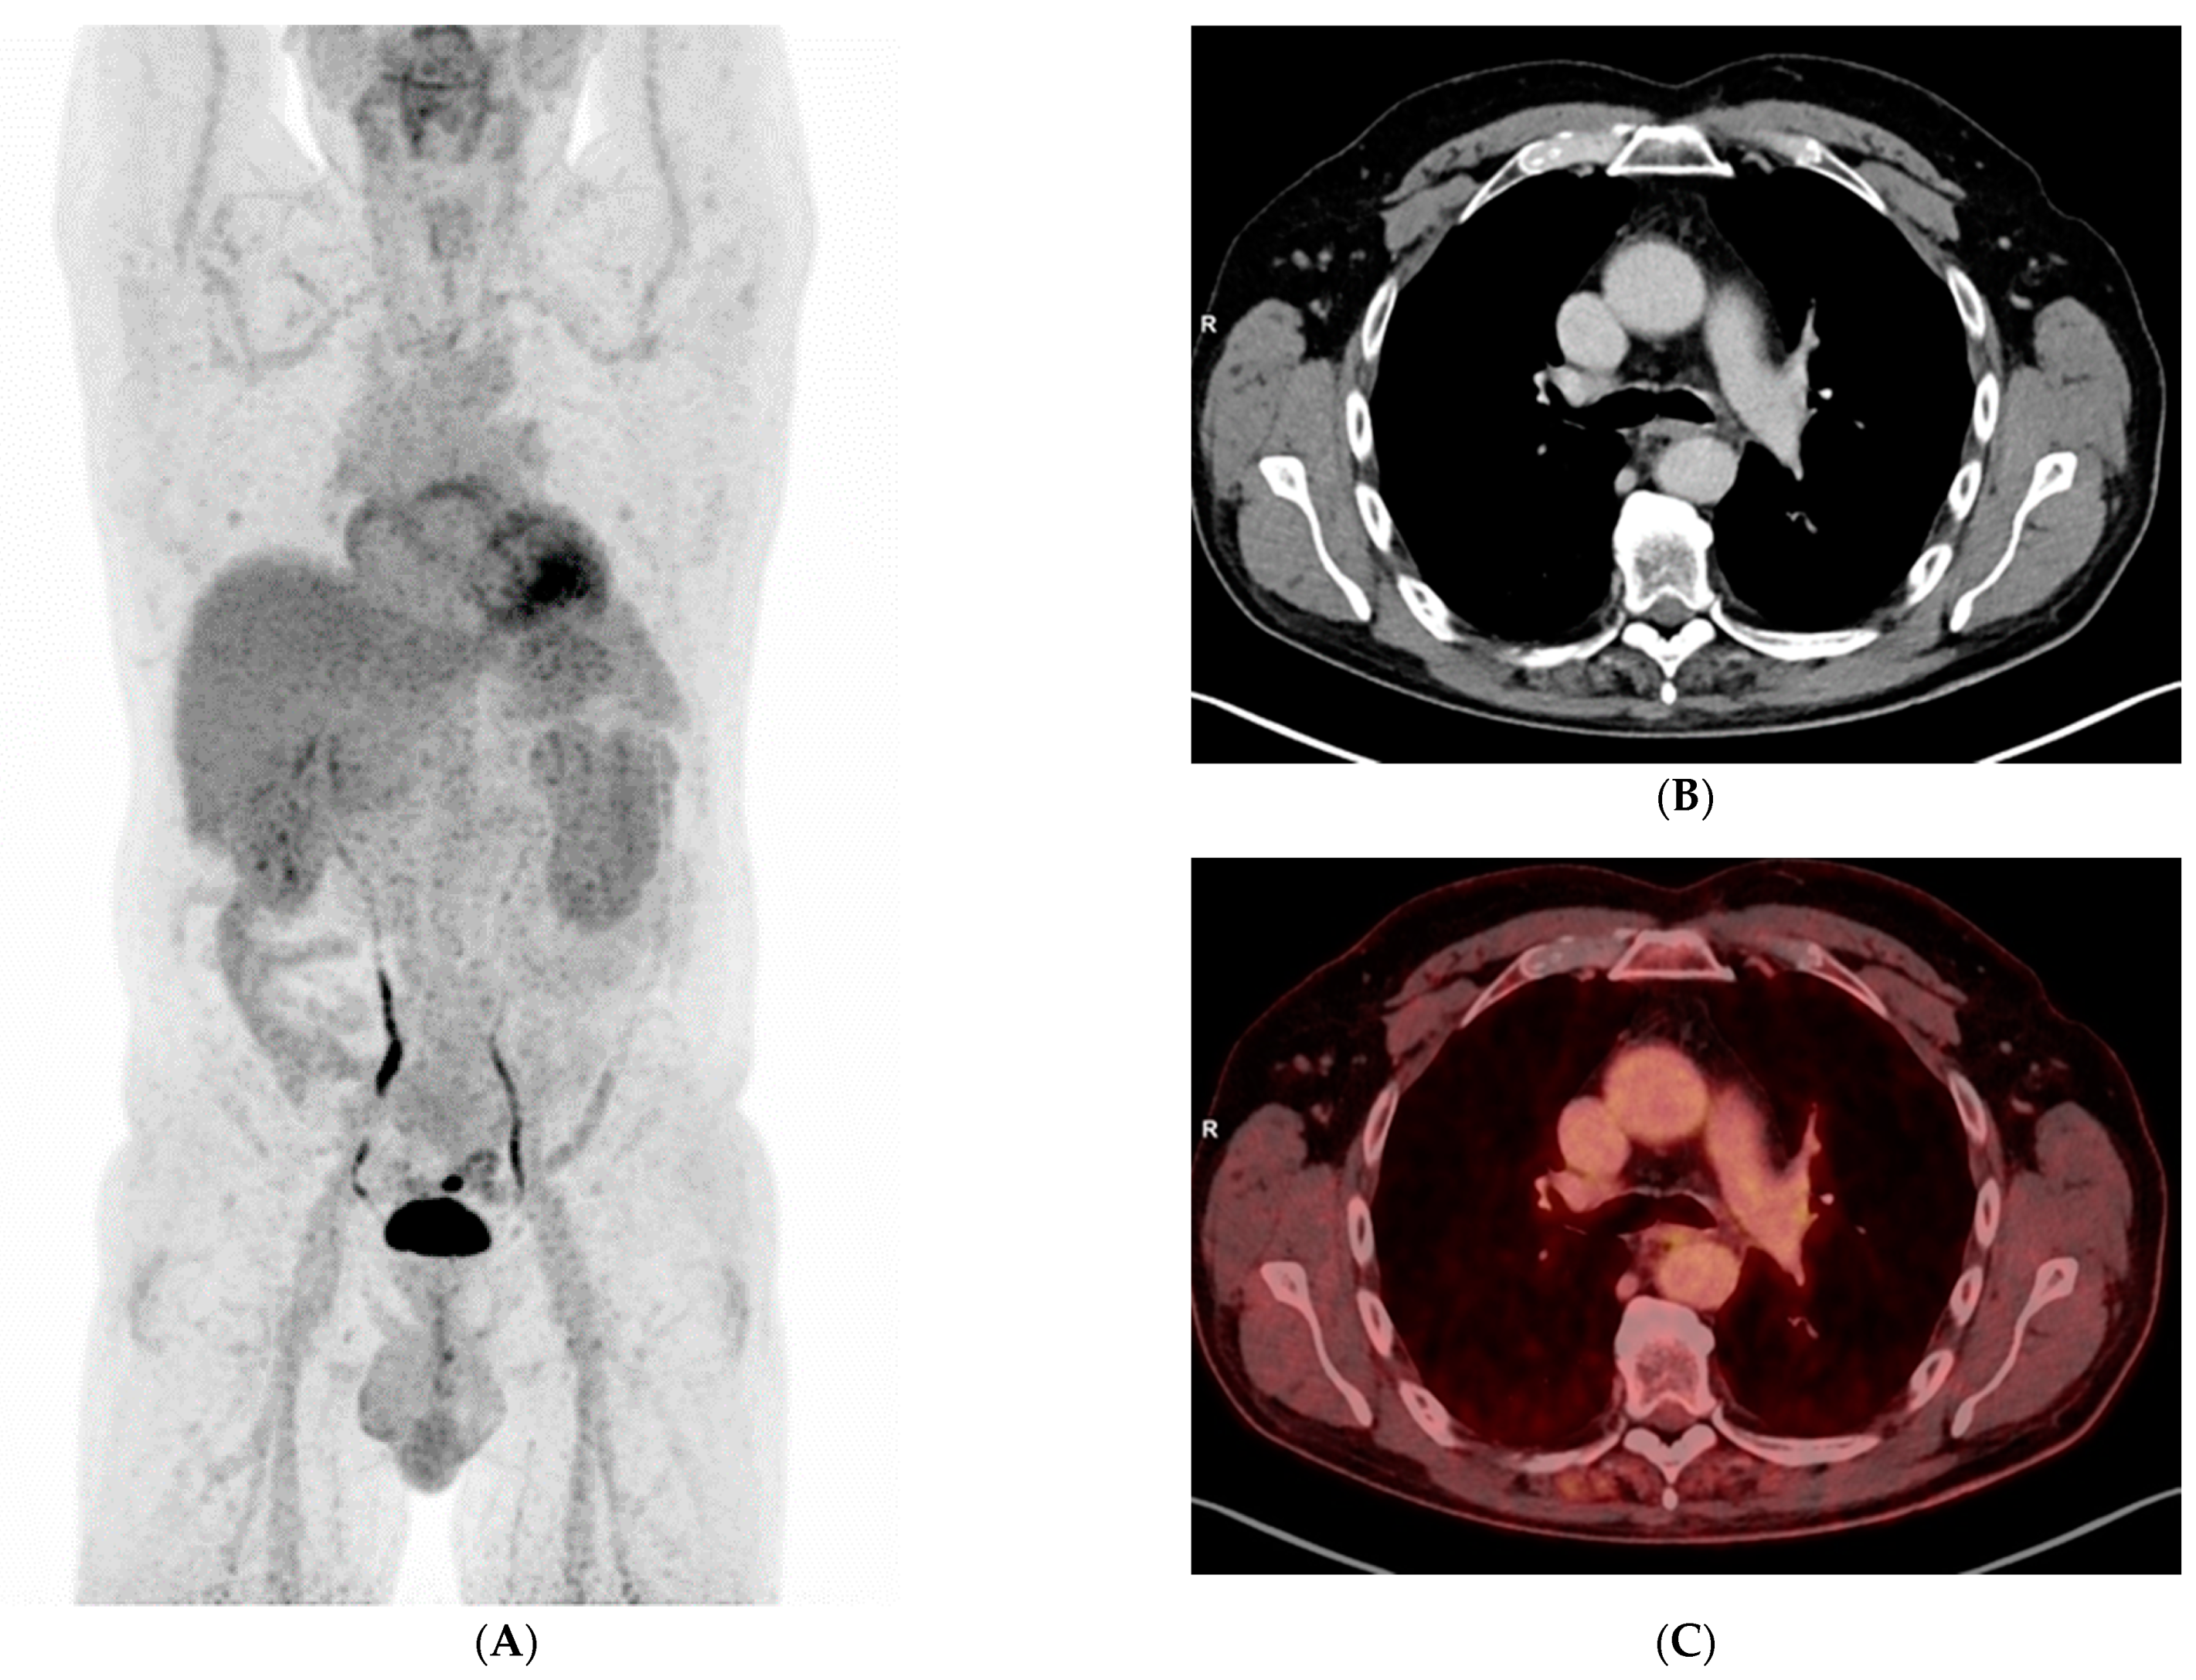

Uncommon Presentation of Granulomatosis with Polyangiitis Mimicking Metastatic Lung Cancer

3. Results